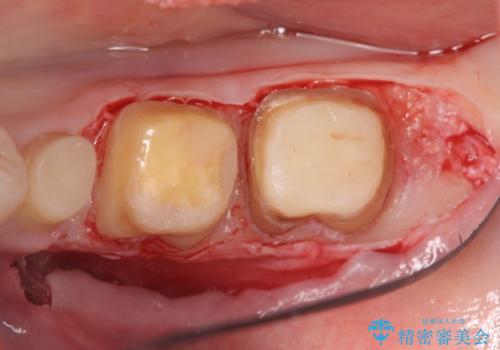

- 左下の歯が虫歯により崩壊し、歯ぐきからの出血も毎回歯ブラシを行う際に出ることから治療を求めて来院されました。

現在装着されているクラウンを除去したところ、クラウンマージンが歯肉縁下となり歯ぐきの炎症が認められたため再度オールセラミッククラウンを製作する前に歯周外科手術を行い歯ぐきの状態を改善しました。